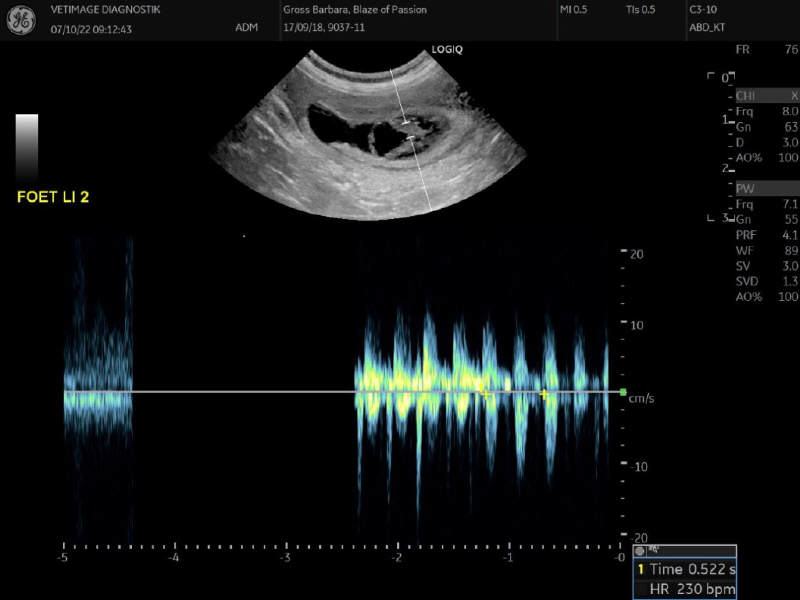

7. Oktober 2022 - Blaze und Harley werden Eltern

Wir waren am 7. Oktober beim Ultraschall.

Blaze of Passion smart Mustache und Trels Hudson Hornet (Harley) werden Eltern.

Wir freuen uns sehr über diesen positiven Bescheid.